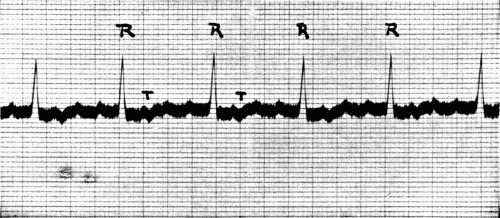

40. Auricular flutter132

41. Auricular fibrillation134

42. Auricular fibrillation134